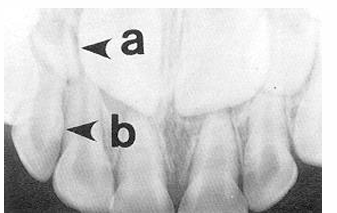

bite wing radiograph

-mesial surface of canine to distal surface of 1st permanent molar

-distal contact of canine to mesial contact of last tooth in arch

occlusal radiographs

occlusal v. periapical radiographs

-occlusal: can often visualize the whole arch, angulation can vary

-periapical: a section of the arch that shows the whole tooth crown to apex- position film as if taking an occlusal